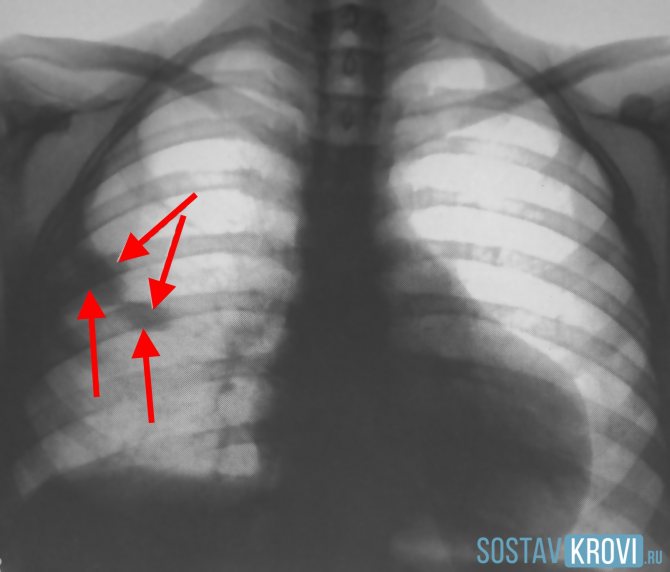

- рентгенологический анализ – определяется парез диафрагмы односторонний, уплотнение очаговое всевозможной формы, расширение корня легкого, наличие выпота без контура, субплевральное расположение и асимметричность тени;

На УЗДГ вен нижних конечностей при инфаркте легкого диагностируется тромбоз глубоких вен. На рентгене легких в боковой и прямой проекциях просматриваются:

- деформация и расширение корня легкого;

- зона снижения прозрачности, имеющая вид клина;

- выпот в плевральной полости.

На рентгене можно увидеть односторонний парез диафрагмы, очаговые уплотнения в лёгком. Как правило, родственники указывают на отсутствие инфекционных заболеваний дыхательной системы, так что достаточно характерные тени на снимке помогает врачу определиться с диагнозом.

На рентгенограмме — негустая клиновидная тень в среднем поле, чаще справа. Ишемизированный участок имеет форму пирамиды, основание которой обращено к периферии, а верхушка – к корню легкого. Характерное треугольное затемнение расположено в средних и базальных сегментах легкого. Дополнительными методами диагностики являются ЭКГ, КТ, МРТ.

При присоединении плеврита выслушивается шум трения плевры. На рентгене хорошо прослеживается характерное затемнение треугольной формы с основанием к периферии легкого в базальных и средних сегментах.